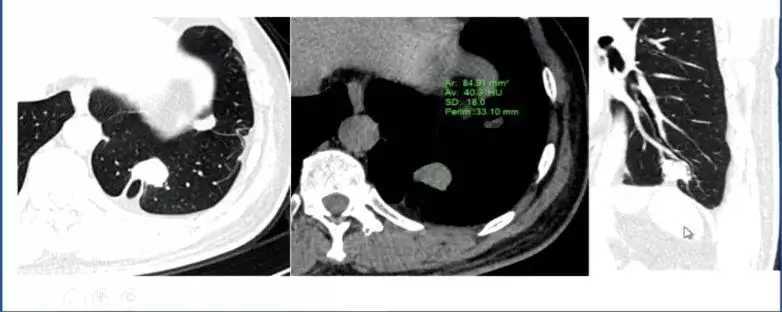

2. 动静脉畸形

肺动静脉畸形经过通过影像技术进行增强处理后诊断明确。

图3 肺动脉畸形